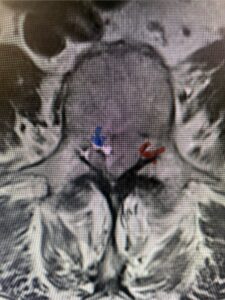

The next patient is a 56-year-old morbidly obese female who had progressive leg pain and weakness. She was over 320 lbs and did not have diabetes either. On MRI she had a massive disc herniation spanning the L3-4 and L-4 interspaces, centered behind the L4 vertebral body (Fig 3A and B). She also had an L4-5 spondylolisthesis. There were opinions that the disc emanated from the L3-4 disc space, but because of spondylolisthesis and on careful inspection of the MRI, there was a high chance the disc herniation had instead emanated from L4-5 (Fig 4). She had conservative treatment including epidurals but had worsening strength and numbness. She was scheduled electively for surgery, but then fell, and broke her ankle. She could not walk, particularly due to the pain down her leg. She was taken to the operating room urgently after she was cleared medically. She had no issues cardiologically and was taken to the operating room. The patient underwent a laminectomy that extended above the L3-4 disc space to below the L4-5 disc space. We encountered mainly centered on the left at the level of the L4 vertebral body and massive disc herniation that created a huge cavity in the lumbar canal. It was covered in an interesting thin membrane that we dissected off the disc herniation (Fig 5). Postoperatively the patient did experience significant relief of pain, but some improvement of strength. In combination with the ankle fracture and the extent of preoperative weakness, the patient required extensive rehab. The patient also developed a seroma and some wound drainage issues that were treated locally.

Fig. 3a : Sagittal T2-weighted lumbar MRI demonstrating a massive L4-5 disc herniation with superior migration behind the L4 vertebral body and taking up most of the left side of the spinal canal (red arrow) Note the slight grade one spondylothesis at L4-5 (blue dash). Notice the severe compression of the thecal sac (blue arrow) by the large left sided disc herniation (red arrow)

Fig. 3b: Axial T2-weighted lumbar MRI demonstrating severe compression of the thecal sac (blue arrow) by the large left sided disc herniation (red arrow) taking up most of the left side of the spinal canal (red arrow)

Fig 4: Sagittal T2-weighted lumbar MRI demonstrating an L4-5 grade 1 spondylolisthesis with obvious emanation of the disc herniation from the L4-5 level (red arrow)